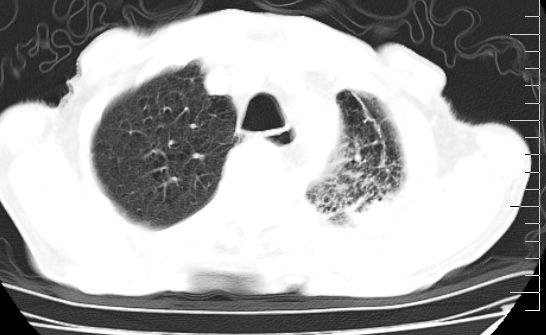

标题: CT10141:男、84岁,咳嗽、咯血1年。 [打印本页]

标题: CT10141:男、84岁,咳嗽、咯血1年。

支持左侧中央型肺癌伴下叶肺不张\\纵隔淋巴结转移.左侧包裹性胸腔积液\\心包积液.左侧少量胸腔积液..慢性支气管炎伴部分间质纤维化.

咯血病史较长,左肺下叶实变,体积未明显缩小,隐约可见血管影及坏死阴影,双肺门及纵隔淋巴结增大,心包增厚积液,纵隔右移位,单侧胸腔积液,首先考虑:大叶型肺泡癌伴纵隔心包转移。